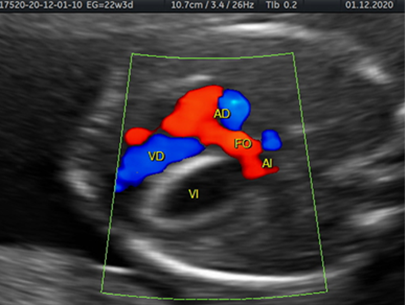

El endocardio experimenta una transición a fibroblastos y produce colágeno-elastina, esta transición y producción de colágeno-elastina se da en la vida intrauterina y en la infancia, cuando el potencial de crecimiento celular sea mayor5. Es por esto que la fibroelastosis endocárdica se caracteriza por una pérdida total de la contractibilidad del ventrículo izquierdo, debido a un desarrollo insuficiente de la musculatura cardiaca y formación de tejido fibroso anormal, condicionando así una severa disfunción contráctil, asociado o no a una estenosis aórtica (Figura 2).

Figura 2 Doppler color que muestra, a través de la válvula mitral en feto con fibroelastosis endocárdica primaria, un llenado diastólico casi ausente en el ventrículo izquierdo (VI) en comparación con el ventrículo derecho (VD). También muestra en Doppler color la derivación de izquierda a derecha de flujo sanguíneo a través del foramen oval.